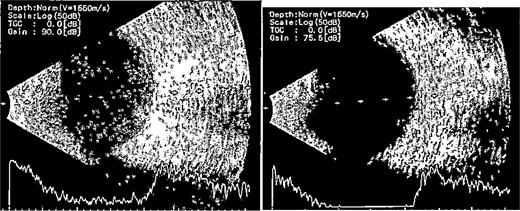

Patient 4: A 74-year-old Sudanese male visited the emergency room with severe left eye pain and loss of vision. His visual acuity was PL; examination showed hypopyon (Fig. 7). B-scan demonstrated vitritis (Fig. 8). He underwent emergency vitreous tap and intravitreal antibiotic therapy.

B-scan ultrasound demonstrating moderate vitreous echoes and vitreous abscess in patient 4.